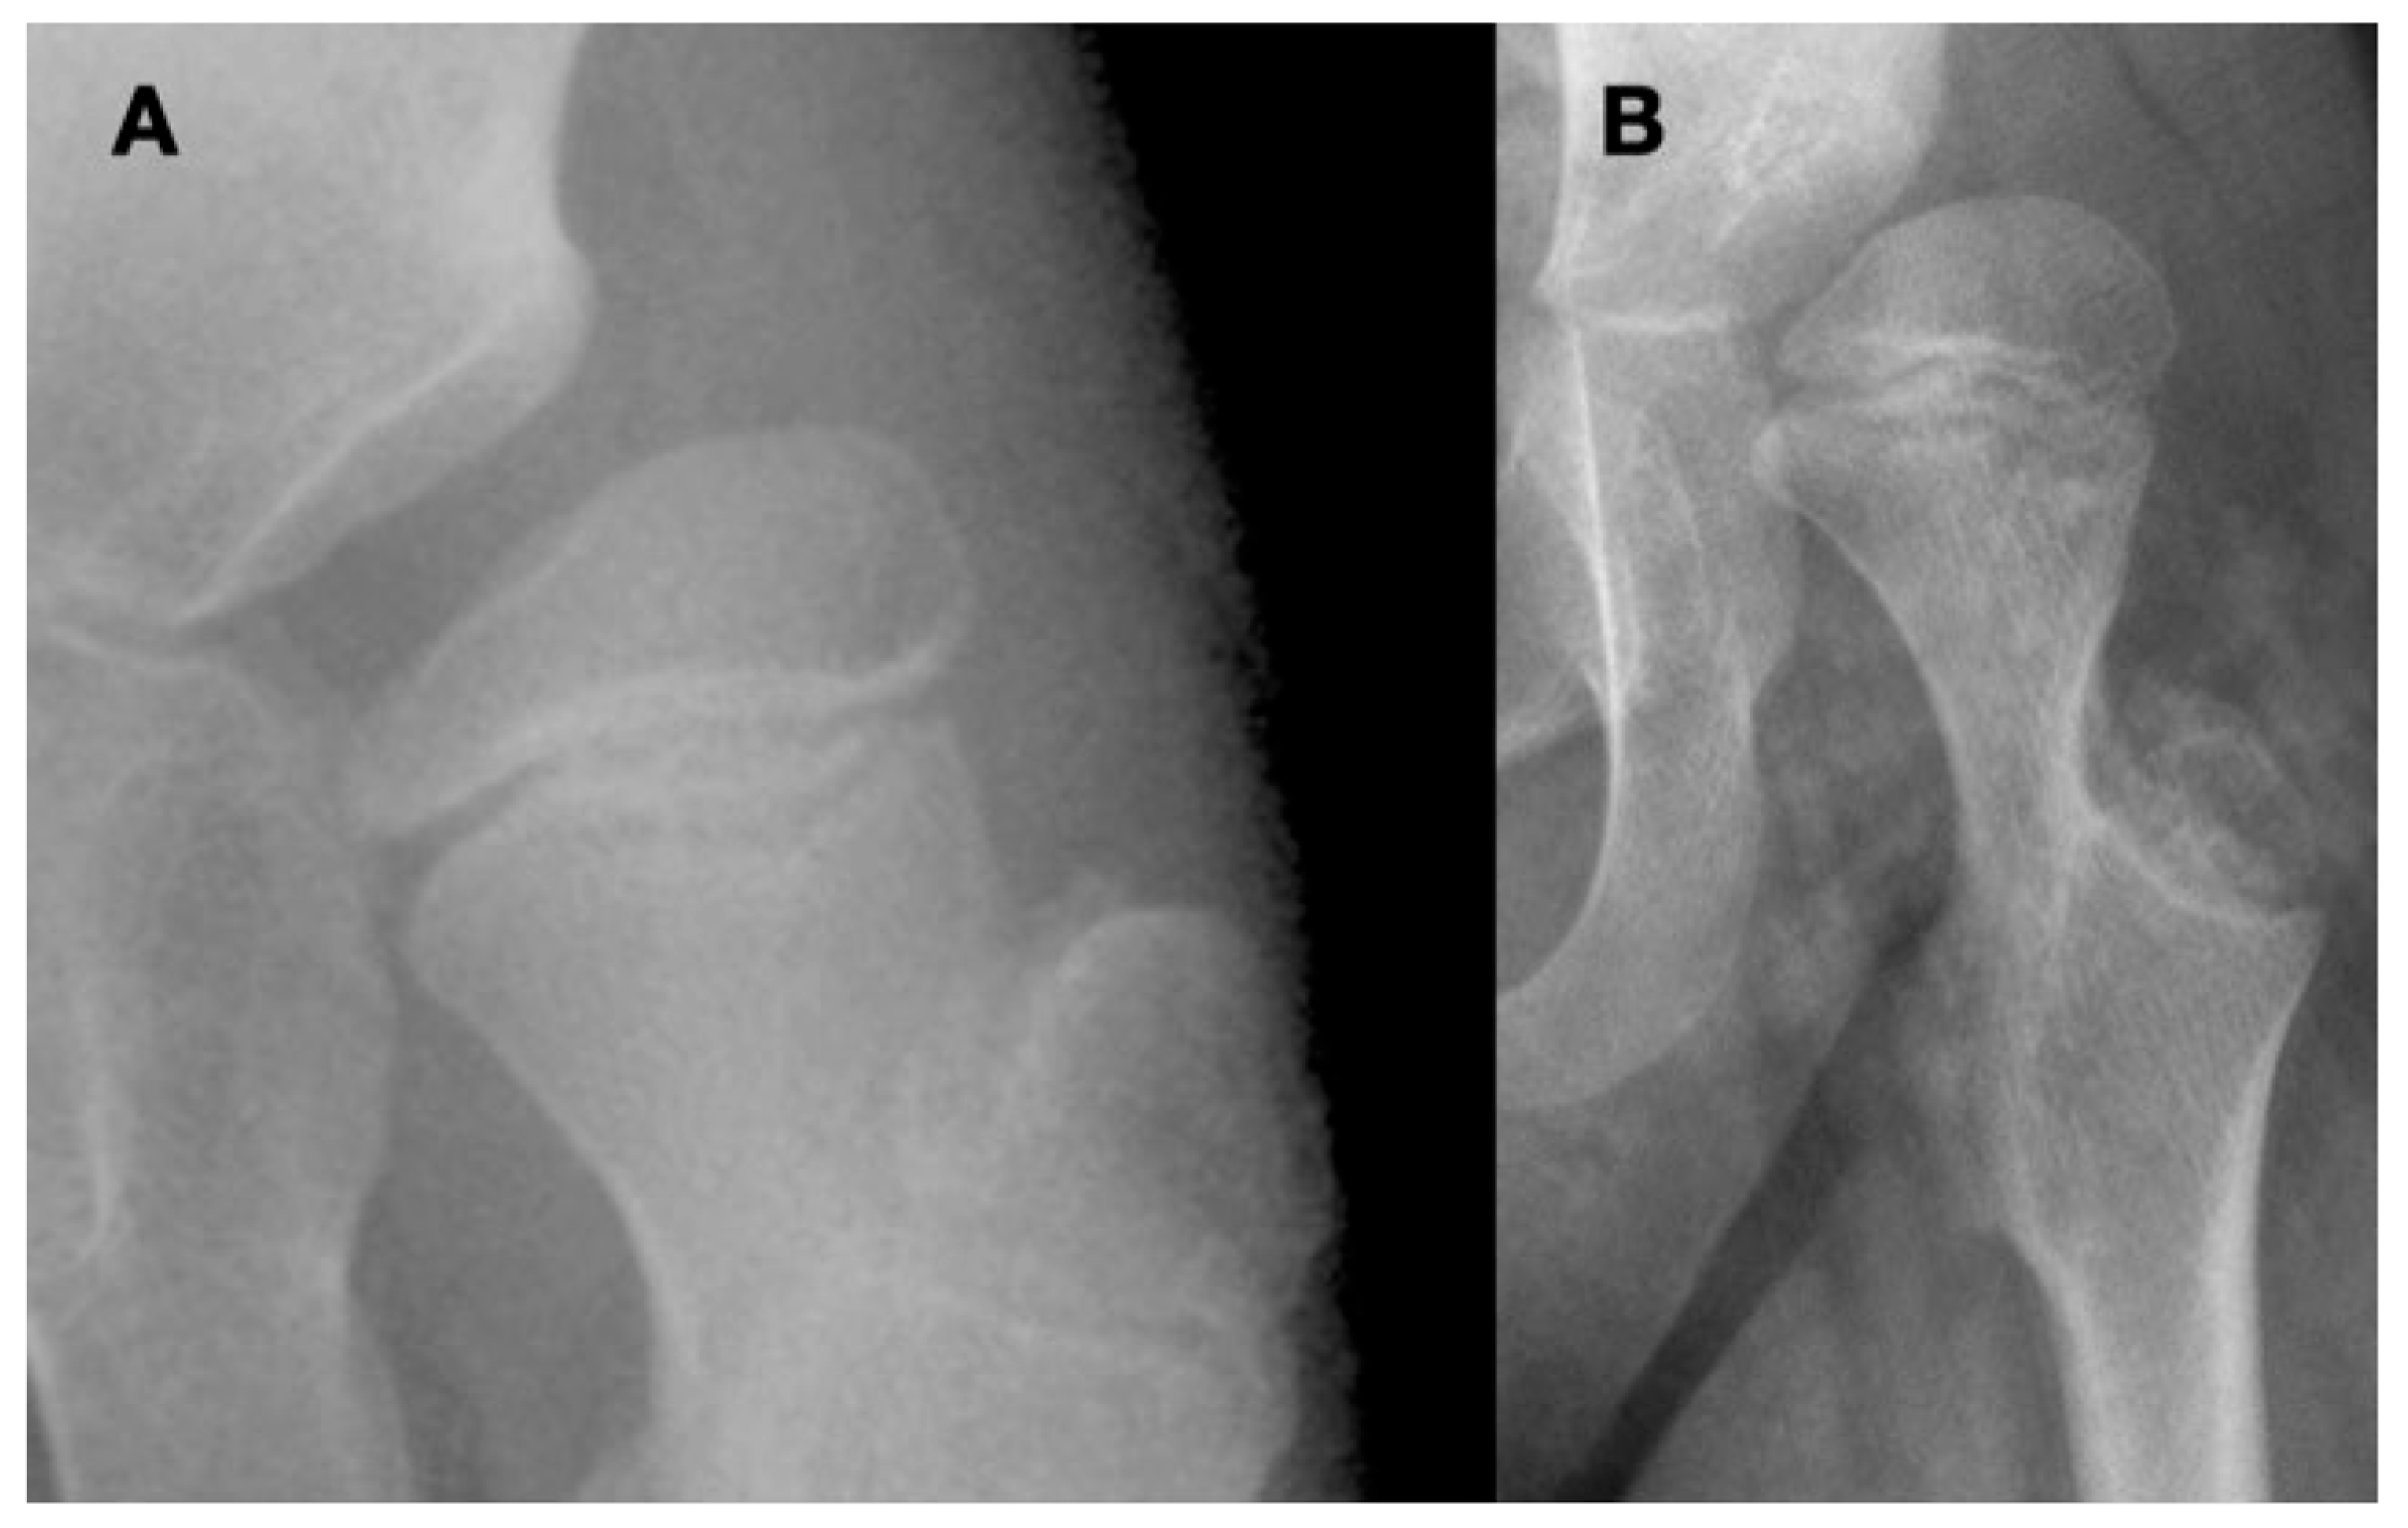

2. Materials and Methods

3.4. Femoral Factors Influencing Hip Pathology

3.4.1. Pathologic Role of Femoral Anteversion

3.4.2. Pathologic Role of Coxa Valga and the Impact of its Correction on Spastic Hips